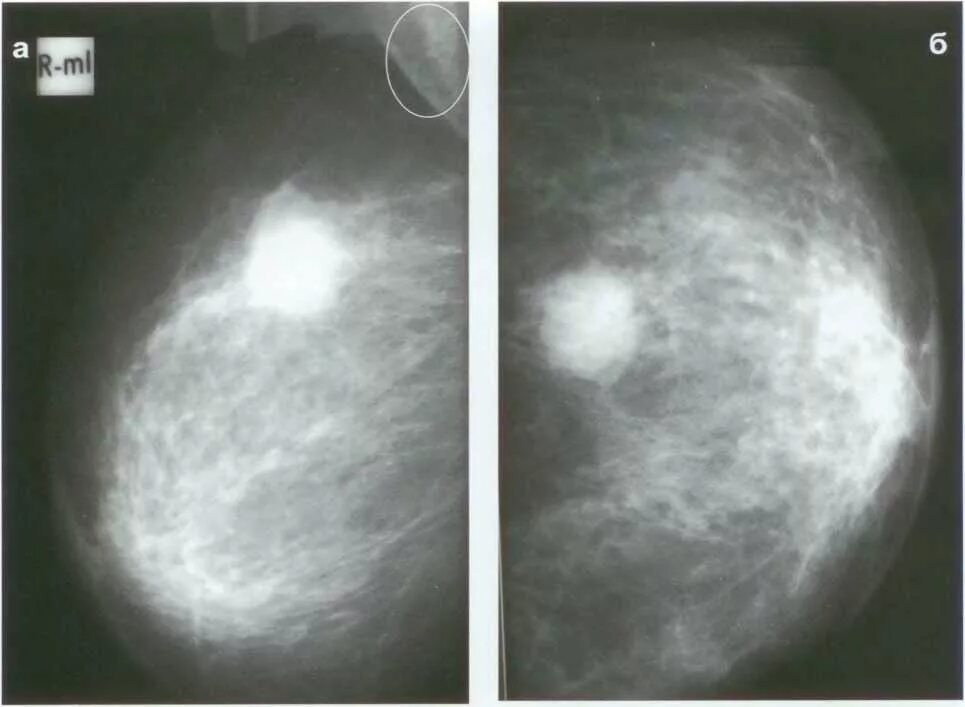

Опухолевидное образование молочной железы